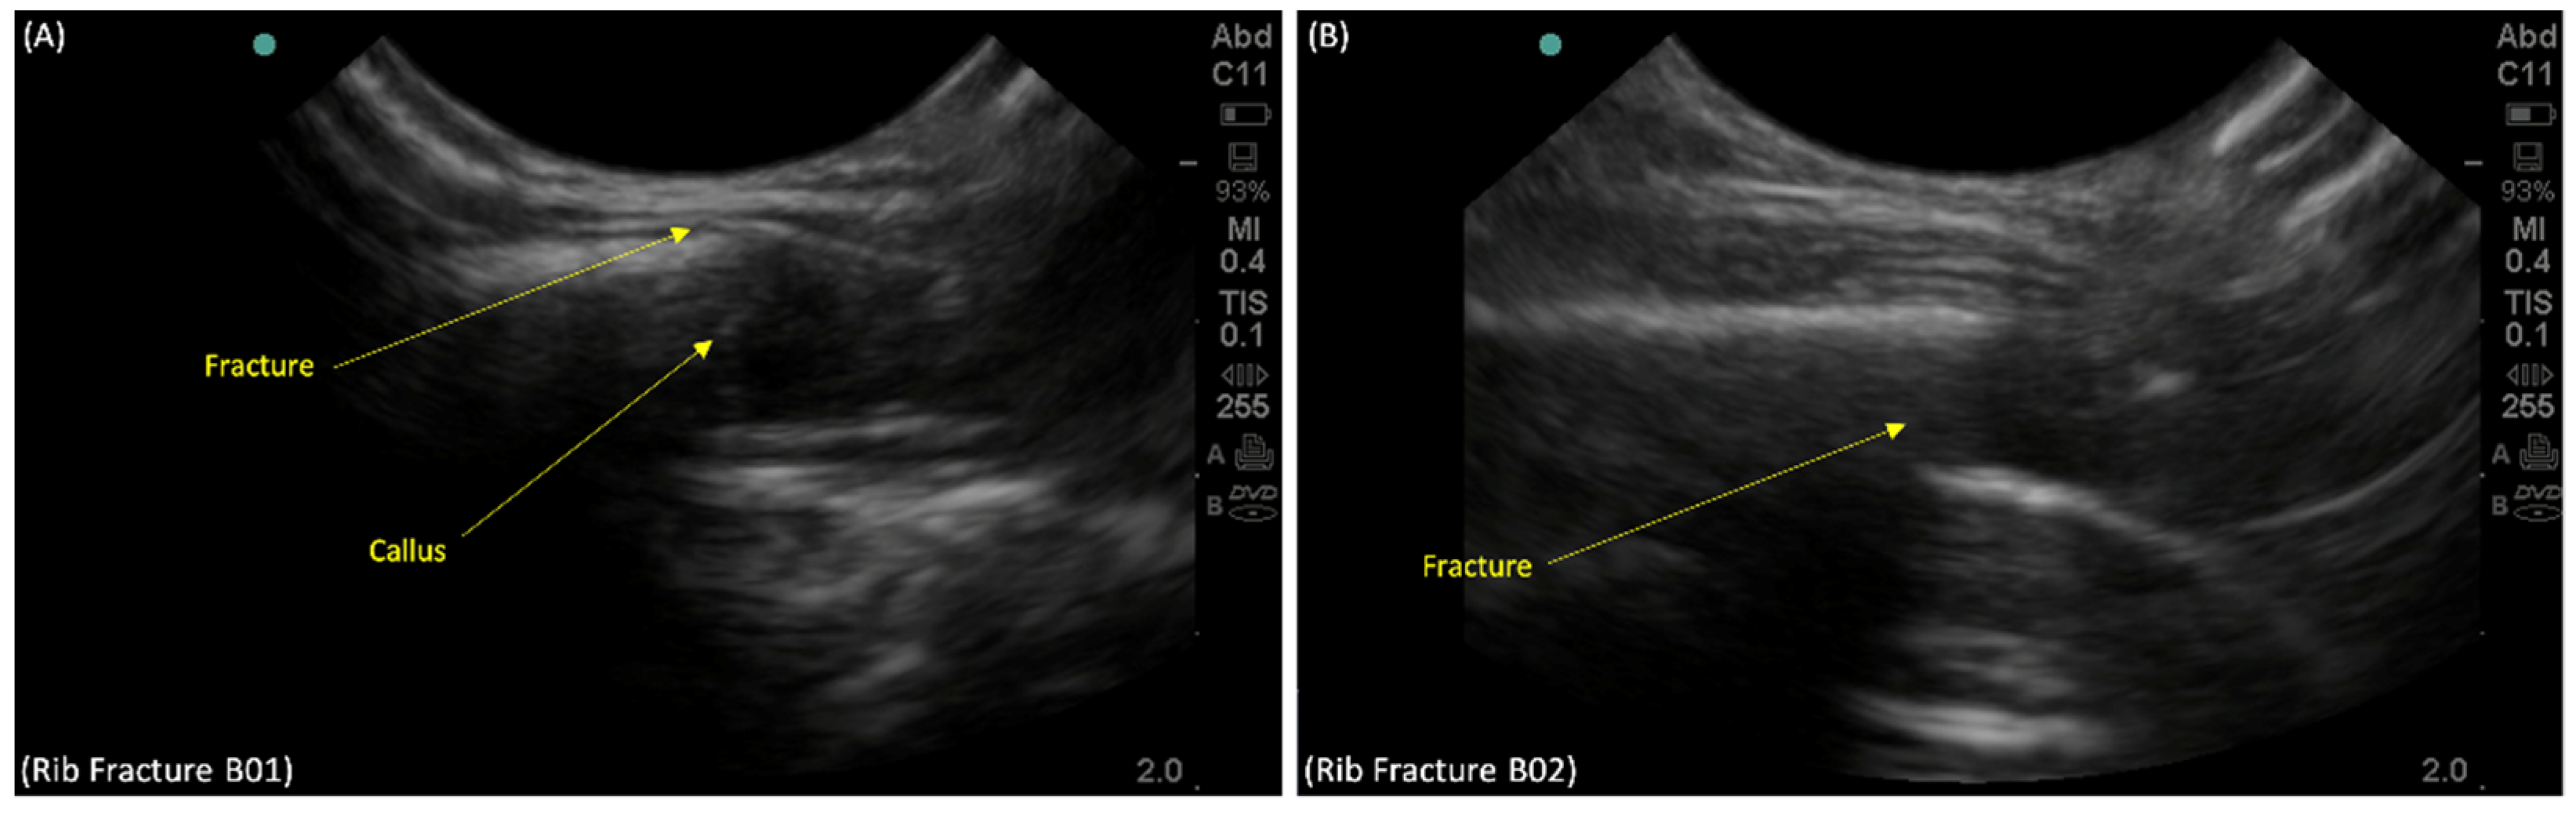

2. Case Presentation